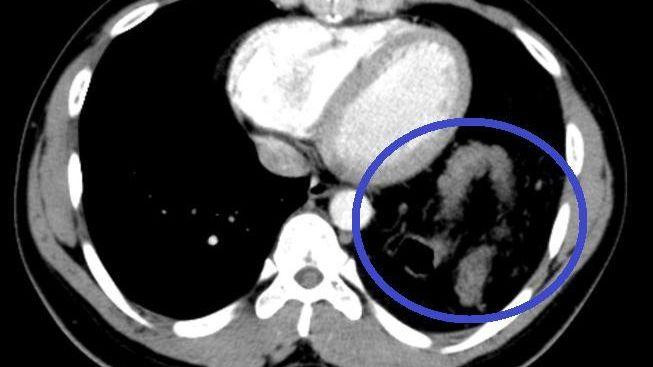

Đại tràng nằm trong ngực trái trên phim cắt lớp vi tính ngực.

Tại đây, bệnh nhân H. đã được chỉ định mổ nội soi để sửa tổn thương và phục hồi cơ hoành. Khi đưa máy soi vào ổ bụng, phẫu thuật viên nhận thấy gần toàn bộ đại tràng ngang, lách, dạ dày và mạc nối lớn đã chui qua cơ hoành lên khoang màng phổi bên trái.

Sau khi đưa các tạng trên trở lại ổ bụng, tổn thương cơ hoành bên trái lộ rõ là một lỗ khuyết rộng khoảng 6x8 cm. Đây chính là nguyên nhân gây ra thoát vị, kết hợp với tiền sử có chấn thương, chẩn đoán trong mổ là thoát vị hoành trái do vỡ cơ hoành.